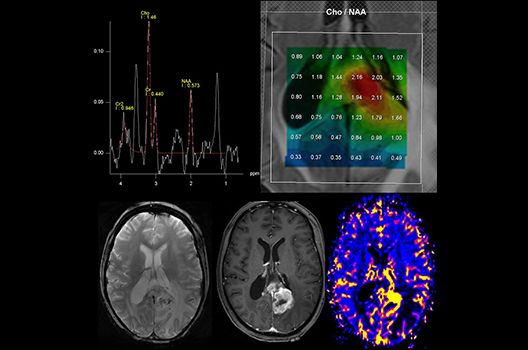

Die Magnetresonanztomographie (MRT) ist ein Verfahren, bei dem durch magnetische Kräfte Bilder des Körperinneren angefertigt werden. In der Neuroradiologie können manchmal kleinste Veränderungen schwere Folgen haben; daher forschen wir an der Entwicklung hochauflösender MRT-Sequenzen, mit denen diese Prozesse und auch einzelne Nervenfaserbahnen sichtbar gemacht werden können. Darüber hinaus sind bei vielen Erkrankungen des Gehirns die Blutgefäße betroffen. Daher arbeiten wir an der Neu- und Weiterentwicklung von MRT-Sequenzen zur Darstellung der Blutgefäße und zur Blutflussanalyse (sog. „Angio-MRT“). Einen besonderen Forschungsschwerpunkt unserer Klinik stellen die MR-Protonenspektroskopie und die funktionelle MRT dar, mit denen die Analyse einzelner chemischer Substanzen im Hirngewebe oder die Darstellung ausgewählter Hirnfunktionen möglich ist.

Die Hybridbildgebung mittels PET/MRT spielt insbesondere in der onkologischen Bildgebung eine wichtige Rolle. Eine mögliche Fragestellung ist die Unterscheidung zwischen einem Tumorrezidiv oder therapeutisch assoziierten Veränderungen insbesondere dann, wenn diese Frage mittels MRT alleine nicht beantwortet werden kann.

Die bildgebende Diagnostik und Verlaufsbeurteilung von Tumoren des Nervensystems ist einer der klinischen und Forschungsschwerpunkte unserer Abteilung. Eine besondere Bedeutung kommt der Hybrid-Bildgebung zu. Das Universitätsklinikum verfügt über einen integrierten Ganzkörper-PET/MRT-Scanner, der die Vorteile der MRT-Bildgebung und der Positronenemissionstherapie (PET) vereinigt. Aufgrund der langjährigen klinischen Arbeit und Forschungstätigkeit mit diesem Gerät hat die Neuroradiologie Tübingen maßgeblich zur Etablierung dieses Verfahrens beigetragen. Auch weiterhin forschen wir intensiv an neuen Methoden zur frühen Einordnung von Tumoren und insbesondere Tumorrezidiven, die mit anderen Methoden häufig nicht erfasst werden können.